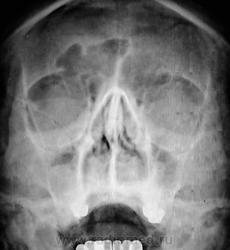

А где верхняя стенка глазницы - нижняя стенка правой лобной?

Фульминантный полисинуит, пневмониеподобная форма с грыжевыми воротами в области нижней стенки.